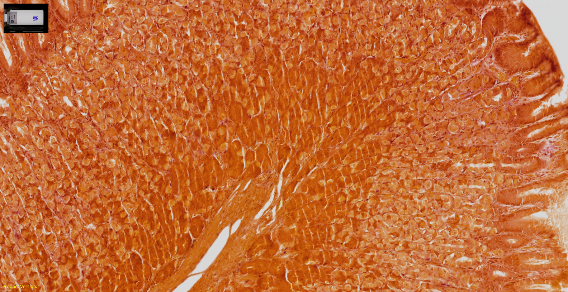

清晰捕捉细胞学样品的图像

SLIDEVIEW VS-M1

其他领军品牌

清晰捕捉各种组织和染色的细节

胃组织,H&E(苏木素和伊红)染色

胎盘波形蛋白(Vimentin)的免疫组化染色(IHC)

人类结肠组织,Warthin-Starry(WS)染色

胃组织,Giemsa染色